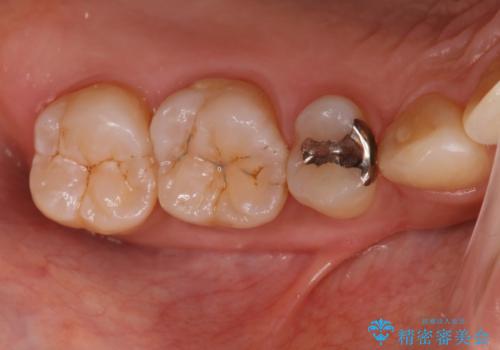

矯正終了し、銀歯が見えるため治してほしい。セラミック治療

担当医 菊地俊介